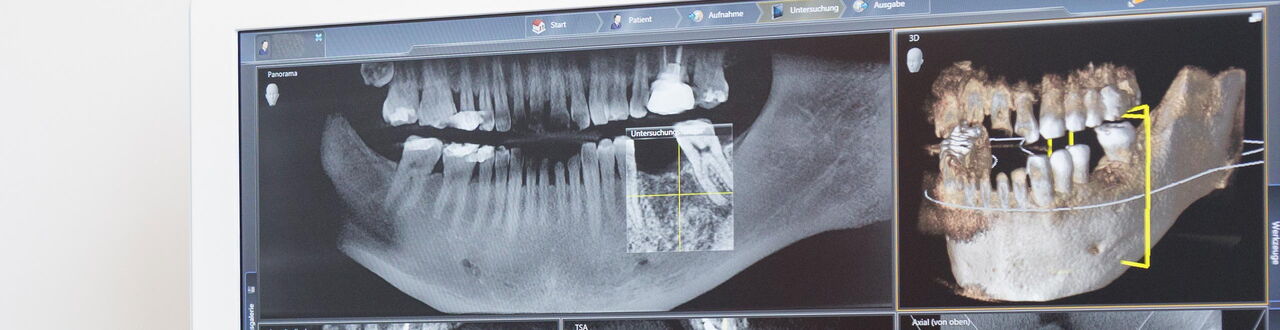

Wir führen zahlreiche chirurgische Eingriffe im Bereich Kiefer, Zahn und Mund durch. Dazu zählen vor allem:

• Zahnextraktion

• Operative Weisheitszahnentfernung

• Kieferorthopädische Chirurgie (Freilegung und Anschlingung von retinierten Zähnen)

• Einsetzen von Implantaten

• Wurzelspitzenresektion

• Knochenaufbau

• Zystektomie

Alle Eingriffe erfolgen durch unsere erfahrene Fachzahnärztin und Expertin für Oralchirurgie Dr. med. dent. Katharina Droste. Sie absolvierte unter anderem eine dreijährige Fachzahnarztweiterbildung im Universitätsklinikum Gießen, in der Abteilung für Mund-, Kiefer- und Gesichtschirurgie. Für uns steht Ihr Wohlbefinden stets im Mittelpunkt – daher legen wir besonders großen Wert auf eine möglichst schmerz- und angstfreie Behandlung. Kürzere Eingriffe können in Lokalanästhesie durchgeführt werden, aufwendigere Operationen sind in Sedierung (Dämmerschlaf) oder Vollnarkose möglich.